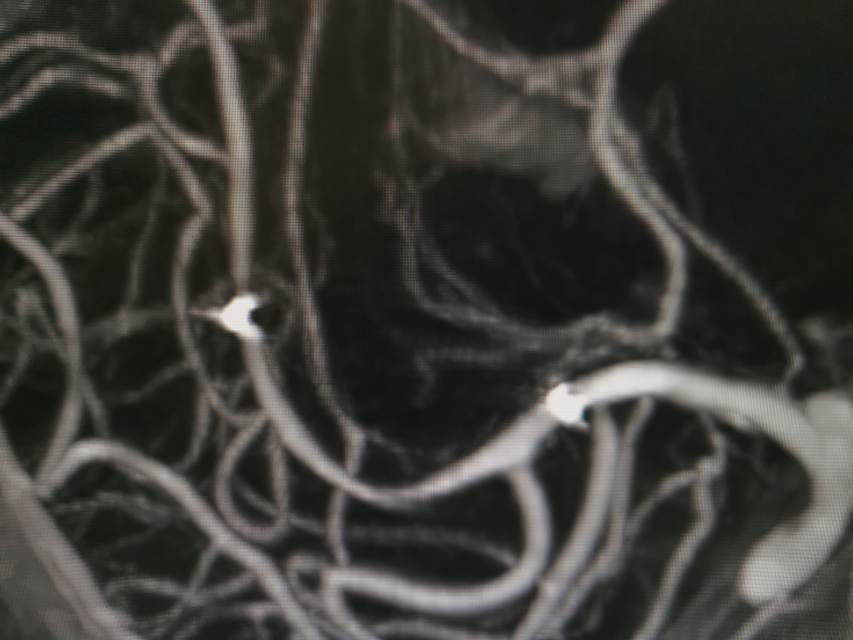

河南信阳帅哥,一个半月前突然出现左侧肢体肌力乏力、认知功能大幅下降、反应迟钝,在当地多家医院按照“脑梗塞”诊治后,症状未能缓解,仍呈进行性加重。经推荐转至我院寻求治疗,术前谈话之后,疫情期间,家里有急事需要处理,唯一的陪人回家了……。今日为患者手术,术中发现右侧大脑中动脉的一个分支出现多节段、长节段的夹层,血流仅剩断断续续的一条线,在血中飘摇,随时存在血管完全闭塞,脑梗塞继续加重,重者可能危及患者生命……,术中正确辨别真腔(误判后果严重),顺利打通重建血管,血流恢复……,手术只是整个治疗过程的一小部分,围手术期仍需要再接再励,帮助患者渡过风险期~~~